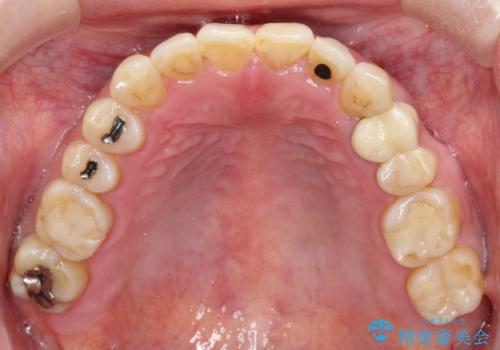

【インビザライン】前歯のガタガタを治したい

- 前歯のガタガタを主訴に来院されました。

上の歯の前突も気になってたため、奥歯の遠心移動も行いながらインビザラインにて治療を行いました。

前歯も下がり満足していただきました。

今回は奥歯の遠心移動とIPRを行って配列しています。